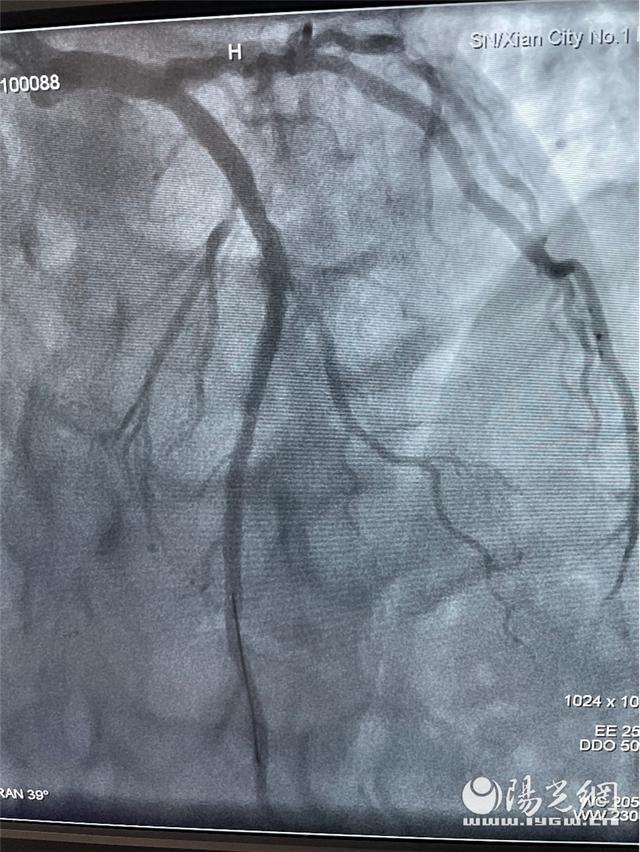

在张誉洋、李同华两位主任和介入室的护士们密切配合,各项救治措施有条不紊的进行着。冠状动脉造影提示:前降支急性闭塞并可见血栓影。导丝通过、球囊扩张、支架植入,整个手术过程用时仅30分钟,患者转危为安。术后患者胸痛症状消失,苍白的脸上再次泛起了红晕,哽咽地说:“谢谢医生护士们救了我的命,在疫情当下,这么紧张艰苦的时期,病毒无情人有情呀!让39岁的我有机会继续履职尽责!”